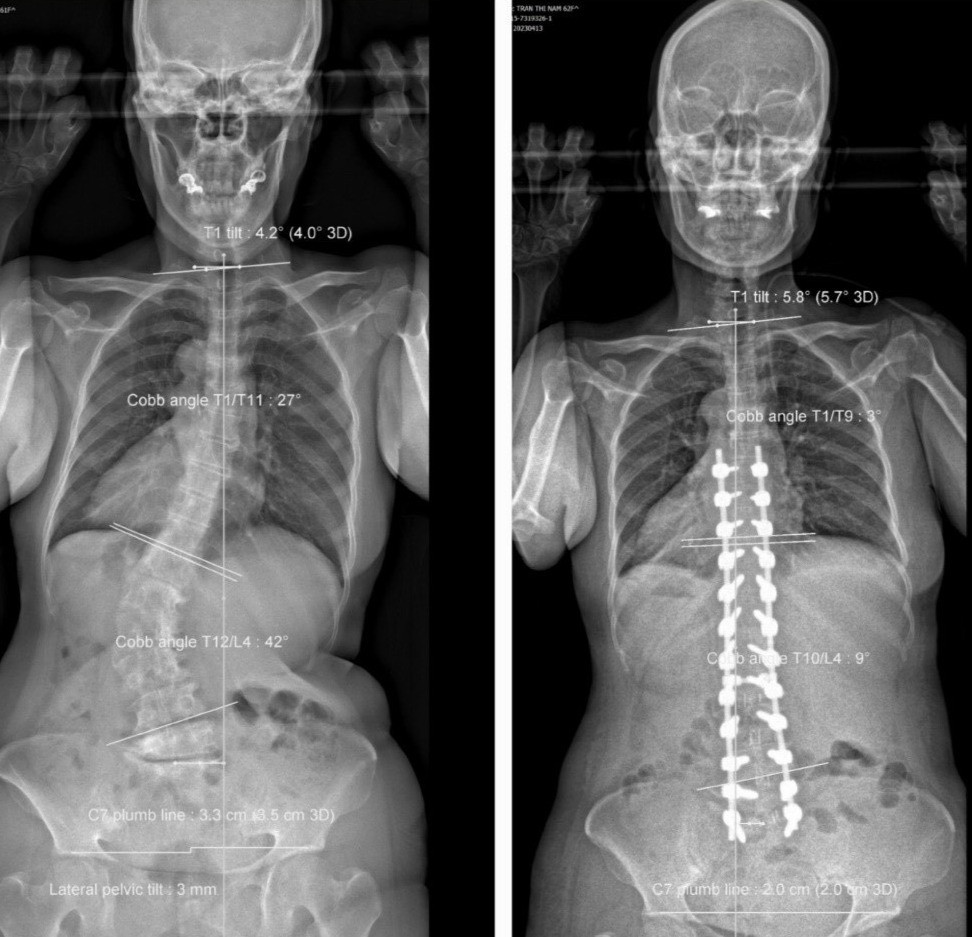

Tại Đơn vị Cột sống, Bệnh viện Trưng Vương, kết quả chẩn đoán hình ảnh bao gồm Xquang-EOS toàn thân và MRI cho thấy bệnh nhân bị vẹo cột sống ngực-lưng (từ ngực 1 đến ngực 11) 27 độ, vẹo cột sống thắt lưng (ngực 12 đến thắt lưng 4) là 42 độ, thoái hóa cột sống, còng cột sống, mất ưỡn cột sống thắt lưng, biến dạng phức hợp khung chậu - cột sống, mất thăng bằng nặng toàn bộ cột sống, đường trọng lực đổ ra trước.

Sau ca phẫu thuật kéo dài hơn 7 giờ 30 phút, bệnh nhân cao thêm 8cm. Hiện dáng đi thẳng, người và phần đầu không còn đổ về trước khi đi hay đứng, hết đau tê hoàn toàn chân phải, chân trái còn tê rất ít, sức cơ hoàn toàn bình phục.